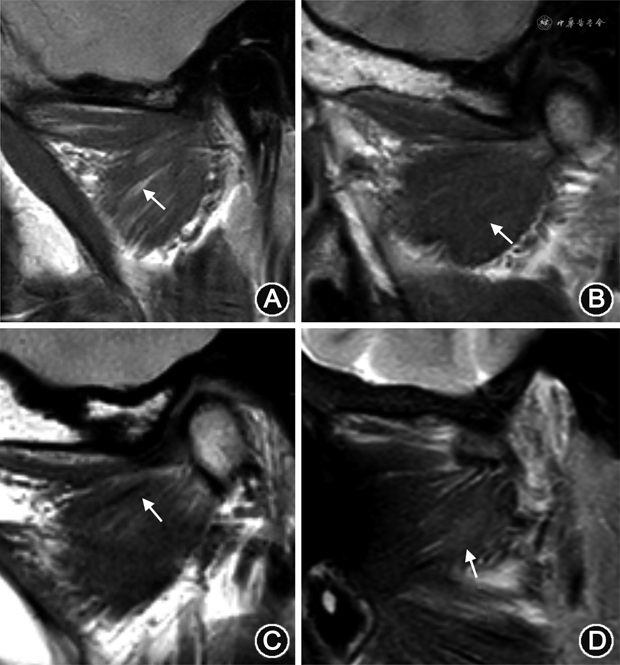

翼外肌萎缩表现为PDWI图像上肌肉内出现脂肪信号替代,但大小无变化(图2A);肥大表现为肌腹体积增大,中部轮廓呈凸出改变,但信号均匀(图2B);挛缩表现为肌腹增大,其内出现纤维化,在PDWI及T2WI-FS图像上出现线样低信号(图2C)[1,11]。翼外肌出现炎症时,T2WI-FS图像出现高信号,表示水肿改变(图2D)[13]。

正常翼外肌上头肌腱在PDWI图像上呈管状均匀低信号(图3A),下头肌腱呈扁平线状均匀低信号(图3B)[14];需要注意的是,Ⅲ型的中间部分的肌腱是由上头底部和下头顶部两束肌腱组成,位于附着点偏外侧份,在PDWI图像上信号与关节盘相仿,易误认为关节盘前移位[7]。肌腱断裂或部分撕裂,是慢性退变和(或)炎症最严重的后果,表现为肌腱纤维全部或部分信号不连续,PDWI及T2信号增高,完全断裂肌腱呈挛缩表现(图3C),部分可见腱鞘周围积液,PDWI及T2WI-FS上呈高信号;增强扫描可见强化[14]。